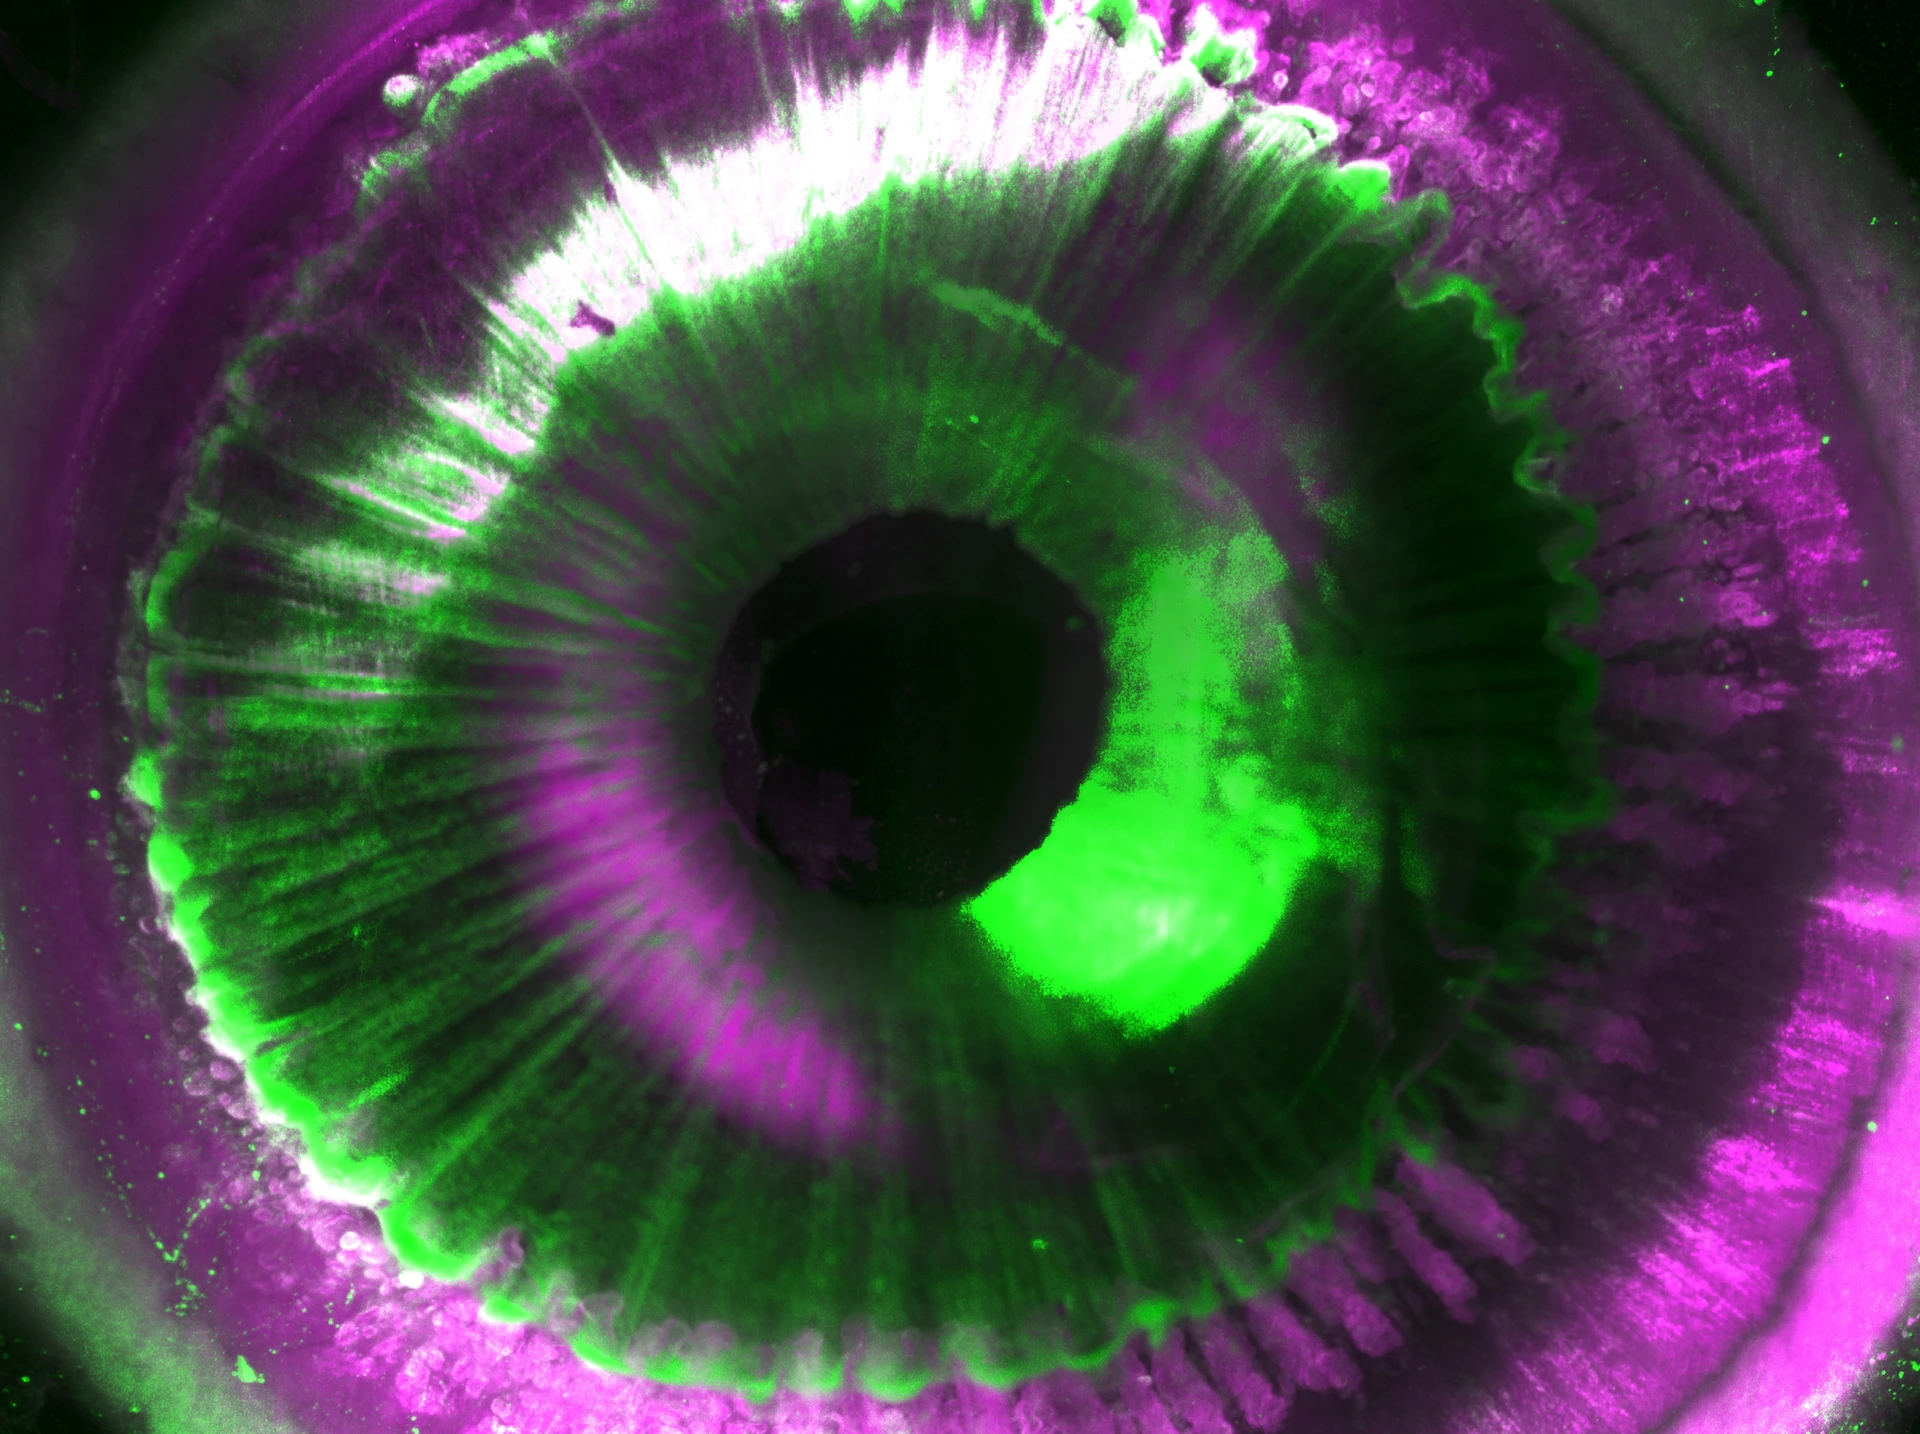

Zelluläre Details eines intakten menschlichen Auges.